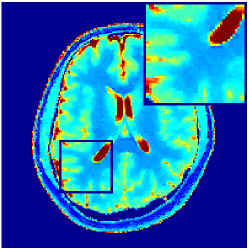

VI-E In-vivo experiments

Two sets of experiments were conducted here: first, we used the 2D and 3D acquisition sequences for scanning a healthy volunteer’s brain (real-world acquisitions). Figures 6 and 7 display the parametric maps reconstructed from 2D spiral and radial readouts. We computed the T1, T2 and proton density (PD) maps using baseline reconstruction algorithms ZF, VS, LR, FLOR, AIR-MRF and our proposed LRTV. While baselines use DM either for quantitative inference or also during reconstruction (i.e. AIR-MRF), we further compare the DM-free LRTV’s performance when cascaded to DM, KM and MRFResnet for quantitative inference. For the 3D spiral acquisitions we compared LRTV and its closest competitor VS in Figure 8. Outcomes from other tested algorithm are displayed in the supplementary materials (Figure S5). Since FLOR does not use dimensionality-reduction, our system ran out of memory during 3D reconstruction; hence results are not reported in this case.

VI-E1 Discussion

The LRTV-DM and LRTV-MRFResnet perform on par, and both outperform all tested baselines for reconstructing T1, T2 and PD maps in all acquisition schemes. This can be observed both visually in Figures 6, 7, 8, S2 and S3, and quantitatively in Table IV across all tested metrics. Other baselines were unable to successfully remove the under-sampling artefacts in TSMIs, and these errors propagated to the parameter inference phase and resulted in inaccurate maps. Temporal-only priors incorporated within LR are shown insufficient to regularise the inverse problem and LR sometimes (e.g. 2D spiral acquisitions) can admit solutions with even stronger artefacts than the model-free ZF baseline. This issue was previously studied for other non-Cartesian MRF readouts that similar to our spiral/radial trajectories, miss to sample the corners of the k-space in all timeframes (see section 2.2.2 and figure 2 in [19]). In the absence of reference for the k-space corners information, the LR iterations despite minimising the objective can converge to solutions with high-frequency artefacts, as visible in the computed maps. This highlights the need for adding an appropriate spatial-domain regularisation. FLOR reduces the LR’s artefacts but this improvement is limited because the suggested nuclear norm penalty does not incorporate an explicit spatial regularisation. Further for reducing artefacts, FLOR can introduce an undesirable bias in the computed T1/T2 maps e.g. see error maps in Figures S2 and S3. The non model-based VS baseline incorporates spatial regularisation and results in spatially smoother maps than ZF and LR, but it is unable to output artefact-free images. Further and consistent with our in-vitro experiment, we observe that VS overestimates the T2 values (e.g. in White and Grey matter regions) in tested 2D acquisitions i.e. the spatial regularisation trades off agains the quantification accuracy. The model-based AIR-MRF adds spatial regularisation through 2D/3D low-pass Gaussian filters however this trades off the sharpness of the computed maps and can increase the errors at the tissue boundaries (we searched Gaussian spreads that keep the blurs and high-frequency artefacts minimal). For our acquisition readouts, Gaussian filters performed better than disk filters of [19] for avoiding strong Gibbs artefacts. On the other hand, the spatiotemporally regularised LRTV greatly improves the TSMI reconstructions i.e. 4 dB enhancement compared to the closest competitor baseline (Table IV). This enables computing accurate and aliased-free multi-parametric inference using DM or the DM-free learning-based alternative MRFResnet as visible in Figures 6, 7, 8, S2 and S3. MRResnet and DM score competitive quantitative inference results i.e. T1 and T2 MAPE less than 5% and 9%, respectively (Table IV). KM also outputs comparably accurate T1 maps, however this shallow learning model despite having a model size larger than MRFResnet, is unable to learn accurate T2/PD quantification and it results in poor estimated maps, consistent with our observations in section VI-C.